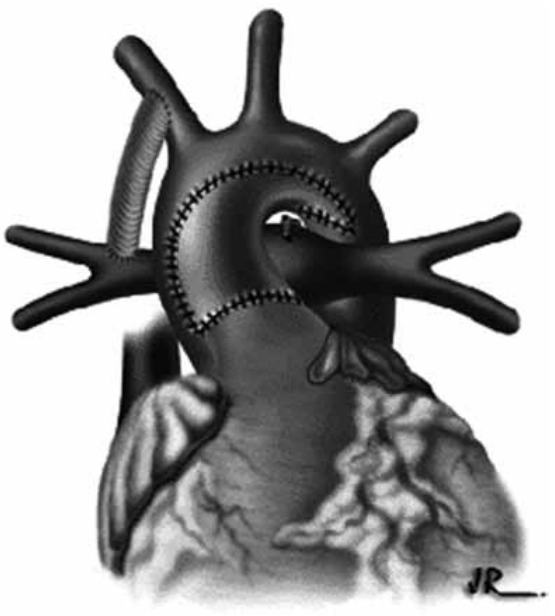

A seguinte figura diz respeito a qual cardiopatia congênita?